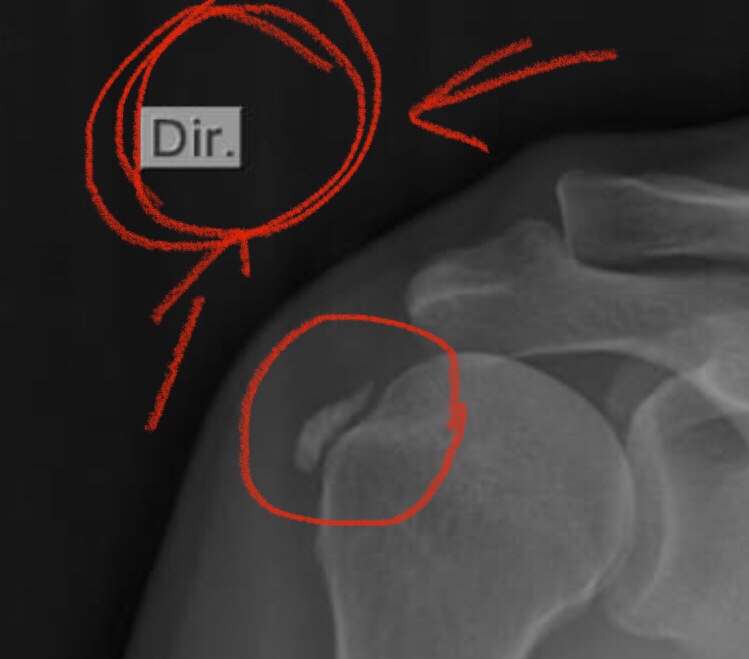

Depois de enfrentar uma bursite, que me deixou algumas semanas de molho, estou retornando aos treinos aproveitando o finalzinho de um recesso. Com o Rio de Janeiro esquentando, após um começo de verão atípico com baixas temperaturas, a escapada para a serra petropolitana era inevitável. E por aqui, a opção mais em conta para quem procura uma piscina para nadar é a filial do Sesi da Barão do Rio Branco.